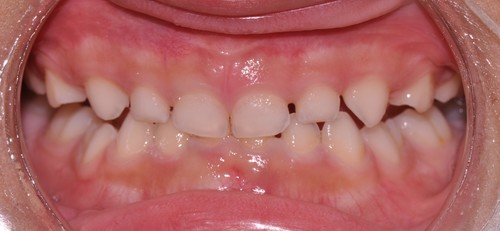

タイプⅠは、いちばんよどのような目的の時に使うかというと、予防・歯列拡大、前突改善、過蓋咬合改善です。歯並びが凸凹しているか、これから乳歯から永久歯に代わったときに凸凹しそうな時に歯列を拡大して、凸凹を予防したり、既に永久歯に代わっているけど凸凹しているときに使用します。凸凹するのは、歯が並ぶスペースが足りないか、歯が大きくて並ばないかですが、成長期にある時期には、歯列を拡大してスペースを作ることを優先します。歯列の拡大といってもいつでも拡大するかというとそんなことはありません。適切な時期を逃してしますと効果が出ないこともあります。乳歯犬歯間の歯列幅が一番大きくなる時は、上顎では真ん中の前歯の萌出1年前から生えるまで、下顎では真ん中の前歯が生えてからその隣の歯が生えるまでといわれています。年齢的には7歳から9歳の間になります。この年齢の前に使うことで、自然な成長を促すことが期待できます。また、下顎は機械的な拡大を期待できるので、積極的に使っていきたいものです。前突改善は、上顎が大きくなるのではなく歯の軸が舌側に傾くことによって改善していきます。過蓋咬合というのは、上の前歯で下の前歯が見えなくなった状態で、上顎の前歯で下顎の自然成長を妨げるようになります。これもプレオルソの得意とするところで、写真のようにきれいになってきます。

↓